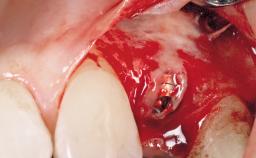

The patient presented with root fracture of the right central incisor with associated distal bone loss. After sectioning and extraction of the fractured root the distal papilla was lost, creating an esthetic compromise. This case demonstrates an option for treating this esthetic compromise. Early (Type 2) implant placement was performed at 7 weeks with simultaneous horizontal and vertical augmentation using Bio-Oss and Bio-Gide (Geistlich). After 3 months a connective tissue graft was performed at the time of implant exposure. Despite these surgical procedures, the papilla could not be recovered. As a result, a prosthetic solution was necessary.